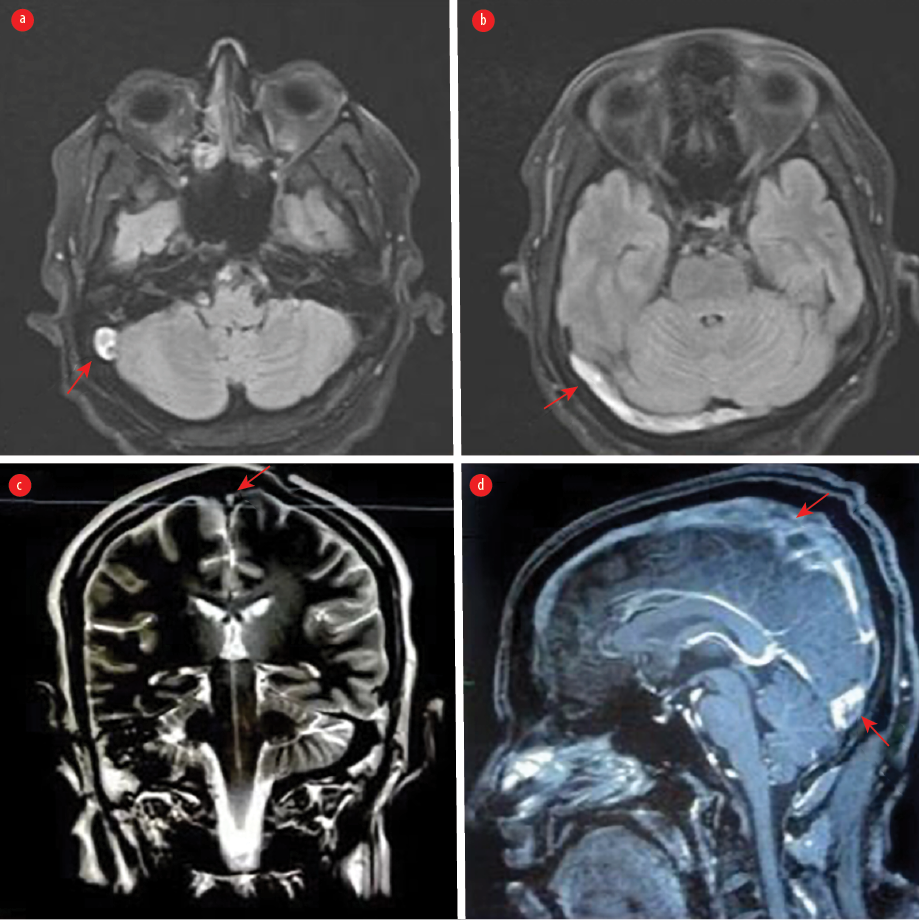

Magnetic resonance imaging of the brain demonstrated increased signal intensity in the right sigmoid sinus and right transverse sinus [Figure 3]. The echocardiogram was normal. Holter monitoring demonstrated sinus bradycardia. Therapeutic anticoagulation was initiated, and the patient recovered clinically despite continuing to experience mild headaches and dizziness. Cardiology evaluation revealed persistent symptomatic bradycardia with sinus bradycardia ranging from 30 to 45 beats/min with pauses lasting 4–5 seconds. After diagnosis of SSS, the patient was transferred to the cardiac care unit for pacemaker implantation. After 24 hours of observation, the post-procedure period was uneventful, and telemetry revealed sinus rhythm without a pacing beat. The recorded heart rate was within the normal range.

Figure 3: (a) An axial T2-weighted MRI demonstrates an area of abnormality with increased signal intensity in the right sigmoid sinus consistent with cerebral venous thrombosis (CVT). (b) Fluid-attenuated inversion recovery weighted MRI demonstrates a hyperintense signal in the right transverse sinus. (c) A coronal T2-weighted MRI shows hypersignal intensity in the superior sagittal sinus. (d) A sagittal contrast-enhanced T1-weighted image shows filling defects along the superior sagittal sinus and involving the other cerebral sinuses, indicating extensive CVT.